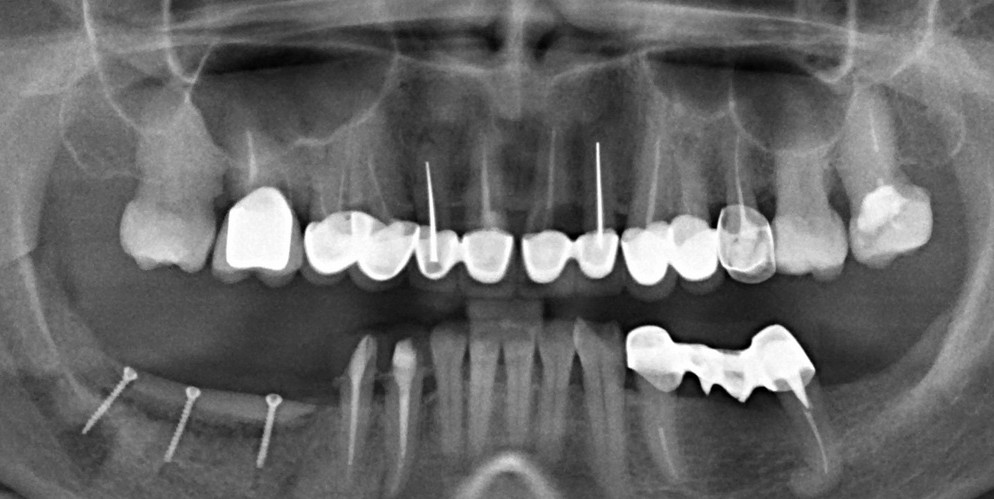

Многие почему-то думают, что основная цель имплантологического лечения — это «вживить» импланты. Типа, добились интеграции, всё хорошо. И не совсем понятно, зачем кто-то заморачивается с синуслифтингом, остеопластикой, пластикой мягких тканей и т. д.?

Cовременными методами остеопластических операций мы можем воссоздать ЛЮБОЙ объем костной ткани в ЛЮБОМ месте зубного ряда. Нюанс лишь в методе операции и сроке, необходимом для нормального восстановления кости.

Предлагаю рассмотреть остеопластическую методику — восстановление объемов костной ткани с использованием аутокостной стружки, биоматериалов и барьерных мембран.

Вопросы: «Какой метод остеопластики выбрать?» или «Какие импланты лучше?» я бы заменил на «Какая схема и методика лечения подойдет данному пациенту?»